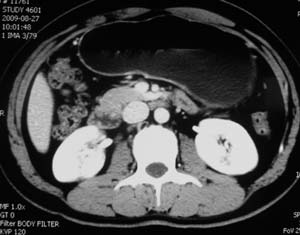

以下是引用子期在2010-3-19 20:47:00的发言:[br]血管畸形的ct增强应该有明显强化,本例并不相符合。本例双肾局部的略低密度影,累及肾盂,局部皮质明显变薄、内陷,增强扫描有轻度的强化,应考虑为炎性病变,患者为年轻男性,累及双肾的感染以结核较常见,可以没有明显的临床症状,尿中有时候也并不能查出什么;肾脓肿常有明显感染中毒症状,本例不符,另外一般的肾盂肾炎或肾小球肾炎通过小便就可确诊,其它还不能排除的是黄色肉芽肿性肾盂肾炎,然而单凭ct一般也很难鉴别。